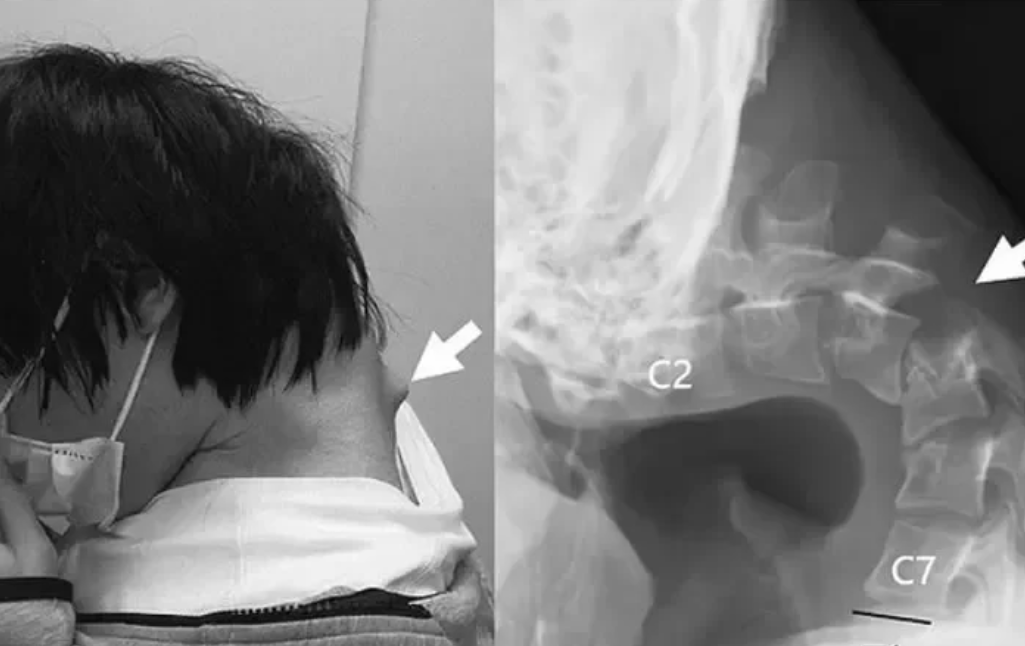

Những bức ảnh gây rùng mình cho thấy một khối phồng lớn nhô ra phía sau cổ bệnh nhân – điều mà các bác sĩ cho là hậu quả từ việc các đốt sống cổ bị “kéo căng quá mức” trong thời gian dài do tư thế cúi đầu không tự nhiên.

Cơ cổ nam thanh niên yếu đến mức không thể tự ngẩng đầu lên. Ảnh: DM

Kết quả chụp chiếu cho thấy các đốt sống cổ của bệnh nhân đã bị biến dạng và lệch khỏi vị trí ban đầu. Mô sẹo giống như mô xơ cũng đã phát triển quanh cột sống theo thời gian do ảnh hưởng của tư thế bất thường kéo dài.